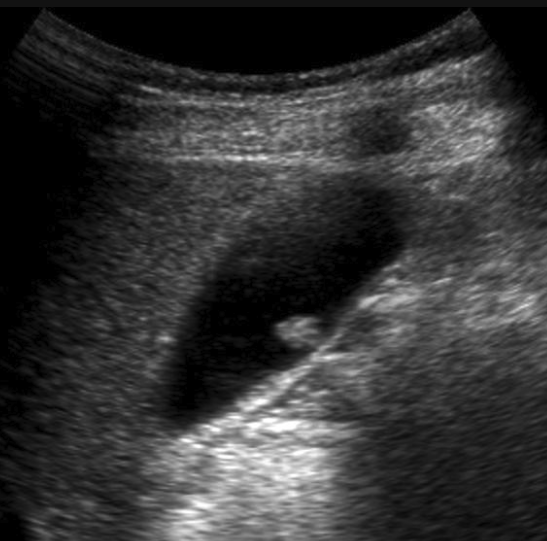

Diagnostic Imaging

To help you learn diagnostic imaging pearls for common primary care presentations